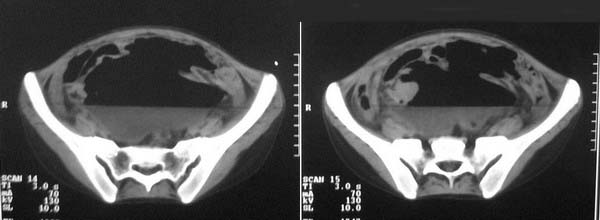

f-18y,腹痛,腹胀,停止排便排气4天,小便正常,四年前阑尾炎手术,病人已手术,明天上传结果。

乙状结肠也扩张

是不是直肠的问题

直肠左侧低密度模糊影,乙状结肠明显扩张,有宽大液平,下腹部肠袢欠规整,内有多发小液平,结合有阑尾炎手术史考虑:直肠周围脓肿,低位肠梗阻,肠粘连。

盆腔巨大脓肿,据术者讲,脓肿大部分壁是有肠管壁形成的,少部分有自己较厚的壁,子宫、附件都泡在脓液里,腹腔肠管广泛粘连,这个病例奇怪的是急性发病,追问不出慢性病史。